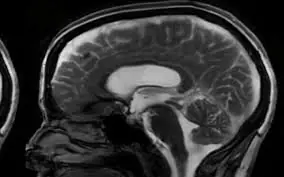

7 Possible Brain Can:cer Symptoms Every Woman Should Be Aware Of